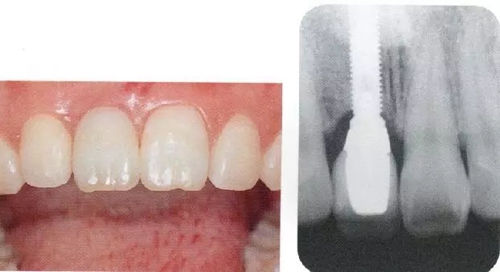

▲圖44-1,2

圖44-3

圖44-1~3 22歲,女性。交通事故3個(gè)月后來院。由于事故導(dǎo)致上頜右側(cè)前牙區(qū)凹陷且存在牙根吸收現(xiàn)象。圖片為初診時(shí)的前方照與根尖片。

圖44-14

同時(shí)期的X光片。

▲圖44-15,16

佩戴最終修復(fù)體時(shí)的正面口內(nèi)照和X光牙片。取得了很好的美觀狀態(tài)。